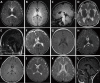

Objective: Hypomyelinating disorders are a group of clinically and genetically heterogeneous diseases characterized by neurological deterioration with hypomyelination visible on brain MRI scans. This study was aimed to clarify the clinical and genetic features of HMDs in Chinese population.

Methods: 119 patients with hypomyelinating disorders in Chinese population were enrolled and evaluated based on their history, clinical manifestation, laboratory examinations, series of brain MRI with follow-up, genetic etiological tests including chromosomal analysis, multiplex ligation probe amplification, Sanger sequencing, targeted enrichment-based next-generation sequencing and whole exome sequencing.

Results: Clinical and genetic features of hypomyelinating disorders were revealed. Nine different hypomyelinating disorders were identified in 119 patients: Pelizaeus-Merzbacher disease (94, 79%), Pelizaeus-Merzbacher-like disease (10, 8%), hypomyelination with atrophy of the basal ganglia and cerebellum (3, 3%), GM1 gangliosidosis (5, 4%), GM2 gangliosidosis (3, 3%), trichothiodystrophy (1, 1%), Pol III-related leukodystrophy (1, 1%), hypomyelinating leukodystrophy type 9 (1, 1%), and chromosome 18q deletion syndrome (1, 1%). Of the sample, 94% (112/119) of the patients were genetically diagnosed, including 111 with mutations distributing across 9 genes including PLP1, GJC2, TUBB4A, GLB1, HEXA, HEXB, ERCC2, POLR3A, and RARS and 1 with mosaic chromosomal change of 46, XX,del(18)(q21.3)/46,XX,r(18)(p11.32q21.3)/45,XX,-18. Eighteen novel mutations were discovered. Mutations in POLR3A and RARS were first identified in Chinese patients with Pol III-related leukodystrophy and hypomyelinating leukodystrophy, respectively.